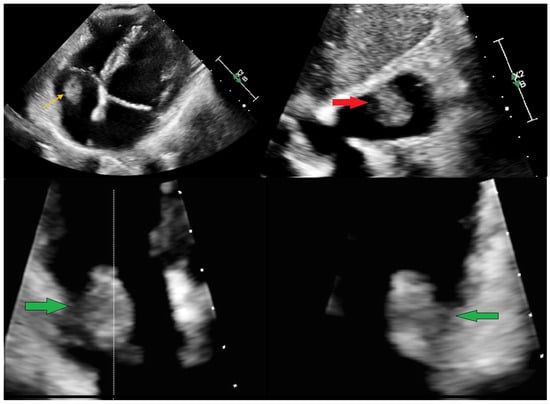

Echocardiography remains a vital part of the initial assessment and monitoring of oncological patients. It allows for proper treatment selection but can also reveal life-threatening complications, including impaired left ventricular function or thromboembolism. It can rarely detect intracardiac masses that require further investigation. In the presented case, a 51-year-old female patient with left-sided breast cancer, who had undergone neoadjuvant chemotherapy, was hospitalised due to a right atrial mass identified via routine transthoracic echocardiography (TTE). Initial anticoagulation therapy showed no clinical improvement. Follow-up TTE revealed a 12 × 19 mm hyperechogenic, mobile mass in the right atrium (RA). Computed tomography angiography (CTA) ruled out pulmonary embolism and revealed that the mass was located close to the tip of the vascular access port. Transoesophageal echocardiography showed that the lesion was not connected to the vascular port. Based on location and mobility, the lesion was most consistent with a cardiac myxoma. After the Heart Team made a decision, endovascular intervention using a vacuum-assisted device was performed without complications. Histopathological examination excluded thrombosis and myxoma, revealing a fibro-inflammatory lesion. A multimodality approach is necessary to assess RA masses. However, even an extensive evaluation could be misleading, so treatment options should always be subject to the Heart Team’s decision. Full article

Figure 1